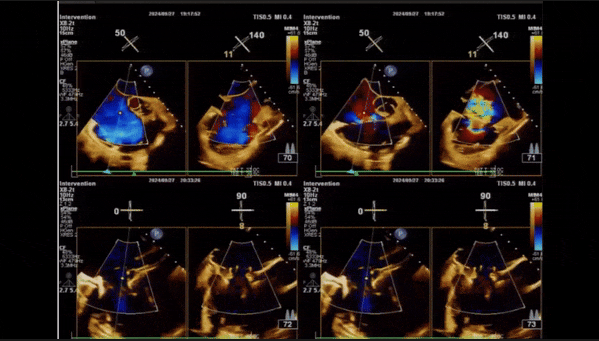

2、彩色多普勒顯示:收縮期三尖瓣口返流束起源于后隔交界、前后葉之間及前隔交界,返流束縮流頸最大寬度27mm,三尖瓣返流口EOA=2.02cm2,返流容積124ml,收縮期三尖瓣返流峰值速度2.64m/s,返流峰值壓差28mmHg,PAPs 43mmHg,舒張期三尖瓣口平均跨瓣壓差1mmHg,肝左靜脈可見明顯逆向血流波。

術(shù)后即刻返流

術(shù)中經(jīng)食道超聲輔助下可見LuX-Valve Plus夾持件抓捕瓣葉狀態(tài)良好,夾持件在位,室間隔錨定位置良好,假體瓣膜整體錨定狀態(tài)穩(wěn)固。

術(shù)后即刻經(jīng)食道超聲可見,三尖瓣假體瓣膜位置合適,牛心包瓣葉運(yùn)動狀態(tài)良好,開閉正常,瓣周及瓣葉對合緣處未見明顯返流,心電圖及心包狀態(tài)較術(shù)前無明顯變化。

術(shù)前術(shù)后返流情況對比